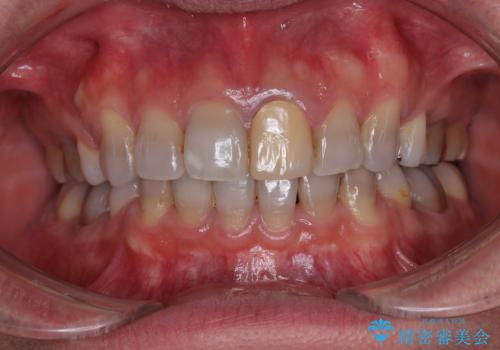

薬剤の影響で変色した歯を自然に オールセラミッククラウンによる審美歯科治療

- 口元の突出感を改善するための抜歯矯正を終えた患者様ですが、幼少期からの変色した歯をセラミッククラウンにて自然な色合いに変えていくこととしました。

口を開けたときに目につく範囲を希望されたため上下ともに8本ずつをオールセラミッククラウンによる補綴治療を行うこととしました。

近年では大変珍しいですが、胎児あるいは乳幼児期の抗生物質の影響で永久歯が変色してしまうことがあります。

ホワイトニングでの改善は期待できないため、オールセラミッククラウンによる補綴治療が必要となります。